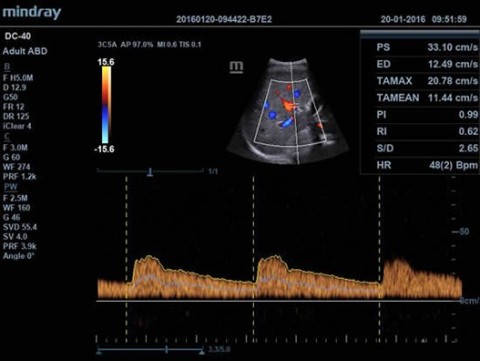

- Режимы сканирования B/M/Цветовой доплер CDI/Цветной M/Энергетический доплер PD/Направленный энергетический доплер Dir.PD

- Импульсно-волновой доплер (включая режим высокой частоты повторения импульсов HPRF)

Доплер:

Да